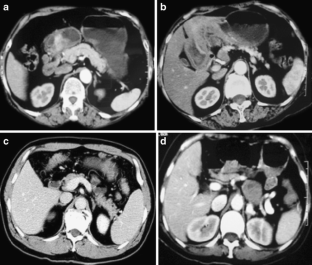

Fig. 3